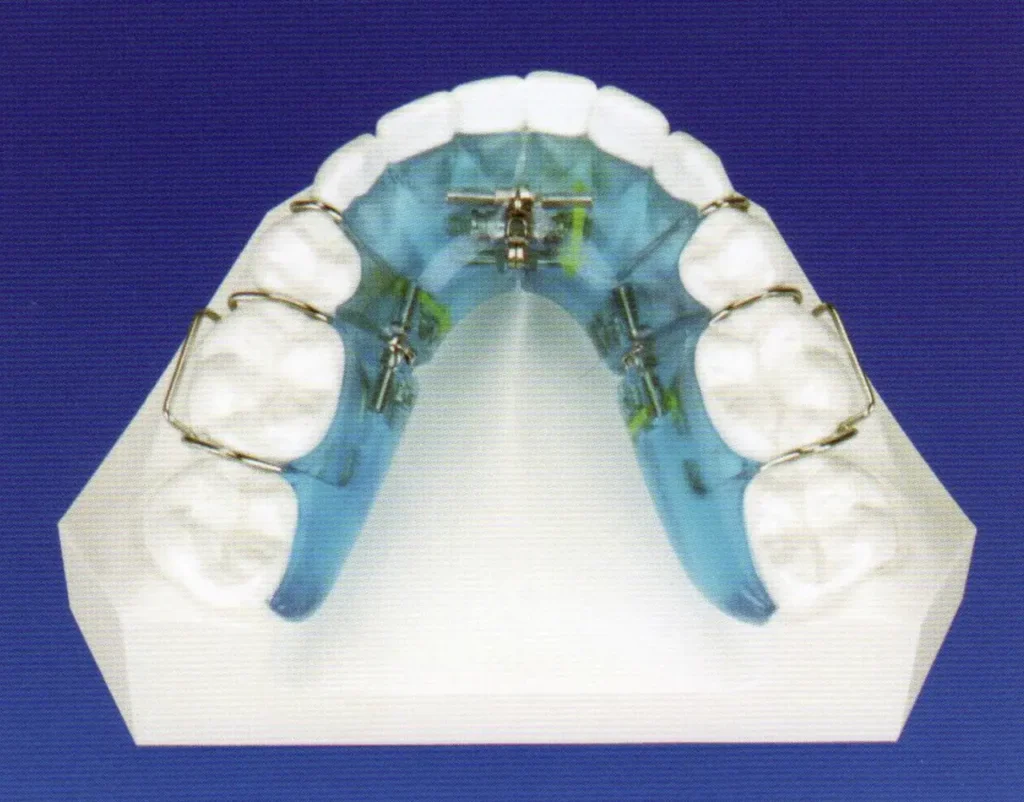

上下顎床矯正装置で顎の幅の拡大(側方拡大)、乳犬歯脱落後リンガルアーチで側方拡大、前後的拡大を行いました。

床矯正装置(シュワルツ床)

リンガルアーチ

成人の場合は、歯を抜いたり、すかしたりして並べますが、小児の場合はあごの発育が望めるためにあごの成長を促したりの治療を行います。リンガルアーチで奥歯が内側に倒れているのを起こして咬み合せも高くなり、あごの横幅も大きく成長を促したりした結果、歯が並ぶスペースも十分に確保できてワイヤー矯正を必要としませんでした。